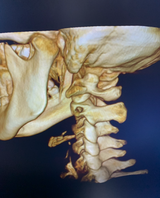

I-CAT Next Gen/FLX delivers an adjustable, large field of view (FOV) cone beam scan up to 17 x 23 cm for the widest range of applications. Advanced features include 3D reconstructions and a fast scan protocol to minimize patient exposure.

Improved Diagnostic Accuracy: CBCT provides three-dimensional (3D) images of the patient's anatomy, allowing for more accurate and detailed assessments of the area of interest.